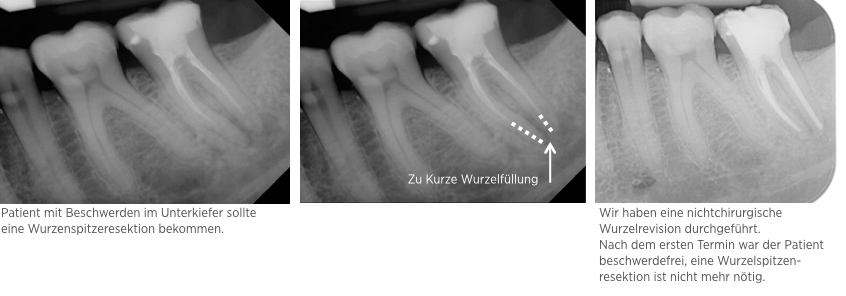

Fallbeispiel: Revision 45 nach Wurzelspitzenresektion (WSR) Recall 30 Monate

Auch Zähne, die bereits eine Wurzelspitzenresektion erhalten haben, können erfolgreich mit einer Revision behandelt werden.